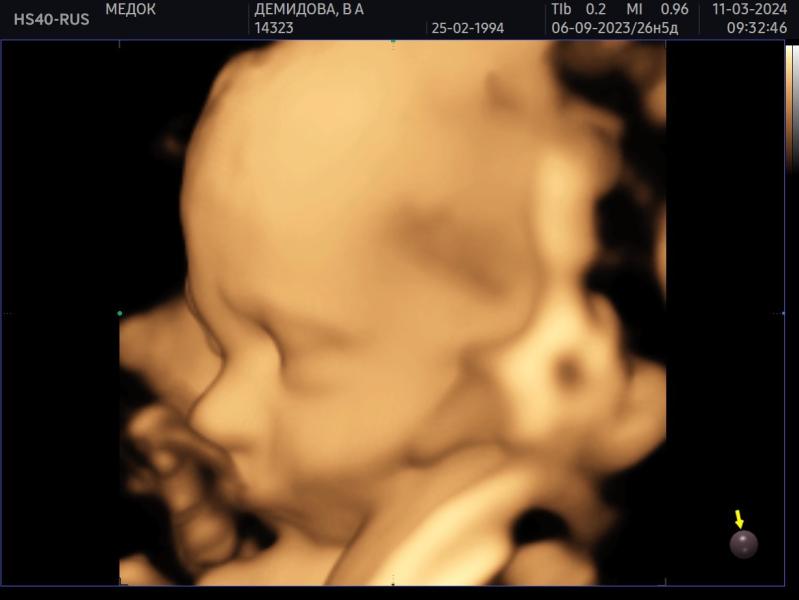

Была сегодня на 3д/4д узи в своей клинике, где веду беременность - Медок Марфино. Узист Лункина ЕГ (вдруг кто тоже туда планирует идти).

Проходила у нее два скрининга, будет у нее же третий, и вот сегодня промежуточное узи.

Срок 27.5 по 1 скринингу, так и опережаем месячные на неделю.

Сын весит около 1163 г. Ваши детки сколько весили на таком сроке?

Врач говорит что хороший вес для этого срока.

В целом все в порядке, лоханки так и остались слегка расширены, но врач сказала это не страшно. ...